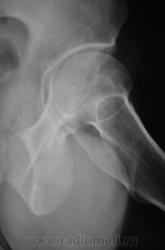

Пациент направлен на рентгенографию тазобедренного сустава с диагнозом ДОА.

очаг в подвертельной области - вряд ли артроз...

Наряду с очагом в головке, видится мне ещё и перелом - линейное нарушение кортикального слоя. И ещё очаг в крыле подвздошной кости (но может и придираюсь). Я бы взял изначально на МРТ таза и тазобедренных суставов.